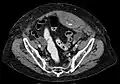

Rectus sheath hematoma seen on axial CT – with active bleeding under Marcoumar- Rectus sheath hematoma as seen on ultrasound[5]

A rectus sheath hematoma is an accumulation of blood in the sheath of the rectus abdominis muscle. It causes abdominal pain with or without a mass.